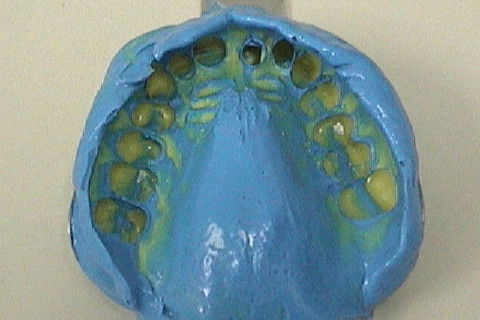

Utilizando osteotomos para expansão da cavidade óssea